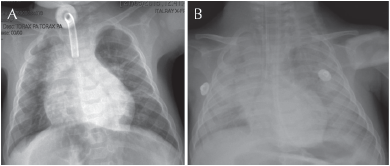

Neumología y cirugía de tórax: estudio endoscópico con laringomalacia grado I, estrechez subglótica concéntrica edematosa que obstruía 80% de la luz de la vía aérea, mucosa granular e irregular que requirieron la ejecución y vigilancia de traqueostomía sin complicaciones, egresó a su domicilio con saturación de O2 de 88% al aire ambiente que mejoró con aporte de oxígeno a 1 L/min a 94%; con estabilidad respiratoria persisten los datos patológicos de reflujo gastroesofágico y en el control endoscópico de seguimiento se advierten: aritenoides edematosas sin colapso de la vía aérea, remisión de la estenosis subglótica sin dificultad para avanzar broncoscopio de 3.6 mm, granuloma en región subglótica y alrededor del estoma que no obstruyen la vía aérea, panendoscopía con datos de esofagitis del tercio superior, se tomaron biopsias y producto de aspirado bronquial para búsqueda de lipófagos y considerar, según resultados, candidato a cirugía antirreflujo por datos de aspiración (Figura 1A).

Infectología: acudió a urgencias por tos, fiebre de 38.5°C con datos de síndrome de respuesta inflamatoria sistémica y dificultad respiratoria, saturación de 82% y radiografía torácica con consolidación basal derecha compatible con neumonía adquirida comunitaria, recibió manejo con penicilina G sódica cristalina, oxígeno suplementario y broncodilatador inhalado, evolucionó con insuficiencia respiratoria y deterioro neurológico que requirió apoyo ventilatorio mecánico con cánula endotraqueal y se ocluyó estoma de traqueostomía con parche adhesivo (Figura 1B).